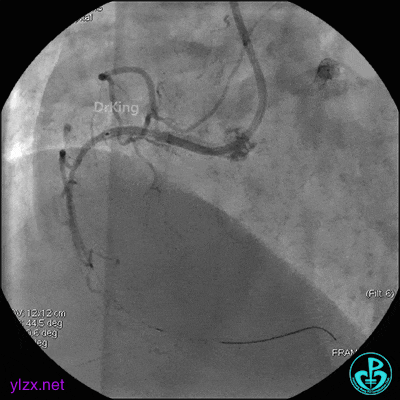

4 急诊冠脉造影

左主干轻度狭窄,左主干到前降支近端钙化影明显。前降支开口严重狭窄,近端闭塞。粗大回旋支轻度狭窄。

右冠脉无严重狭窄,右冠脉没有给前降支提供逆向供血。